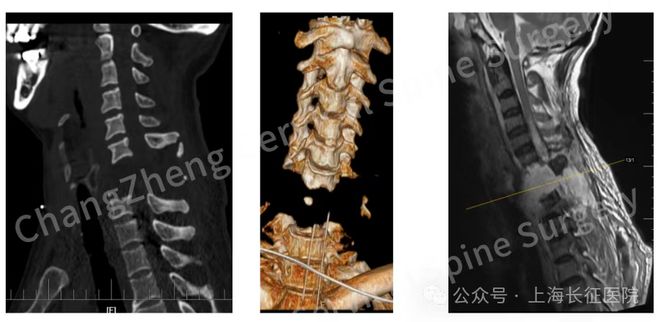

今年 6 月,上海长征医院成功为一例遭遇罕见严重颈椎骨折脱位的患者实施了复位固定手术。

这位患者被送到医院时颈椎发生罕见的大跨度脱位,严重程度可以说是“身首离断”,已造成脊髓严重挫伤、关键神经血管结构撕裂。

在手术团队的努力下,患者安全地度过了手术期,颈椎实现高难度复位,救助过程中所运用的技术在此类极端病例中也是首创的。